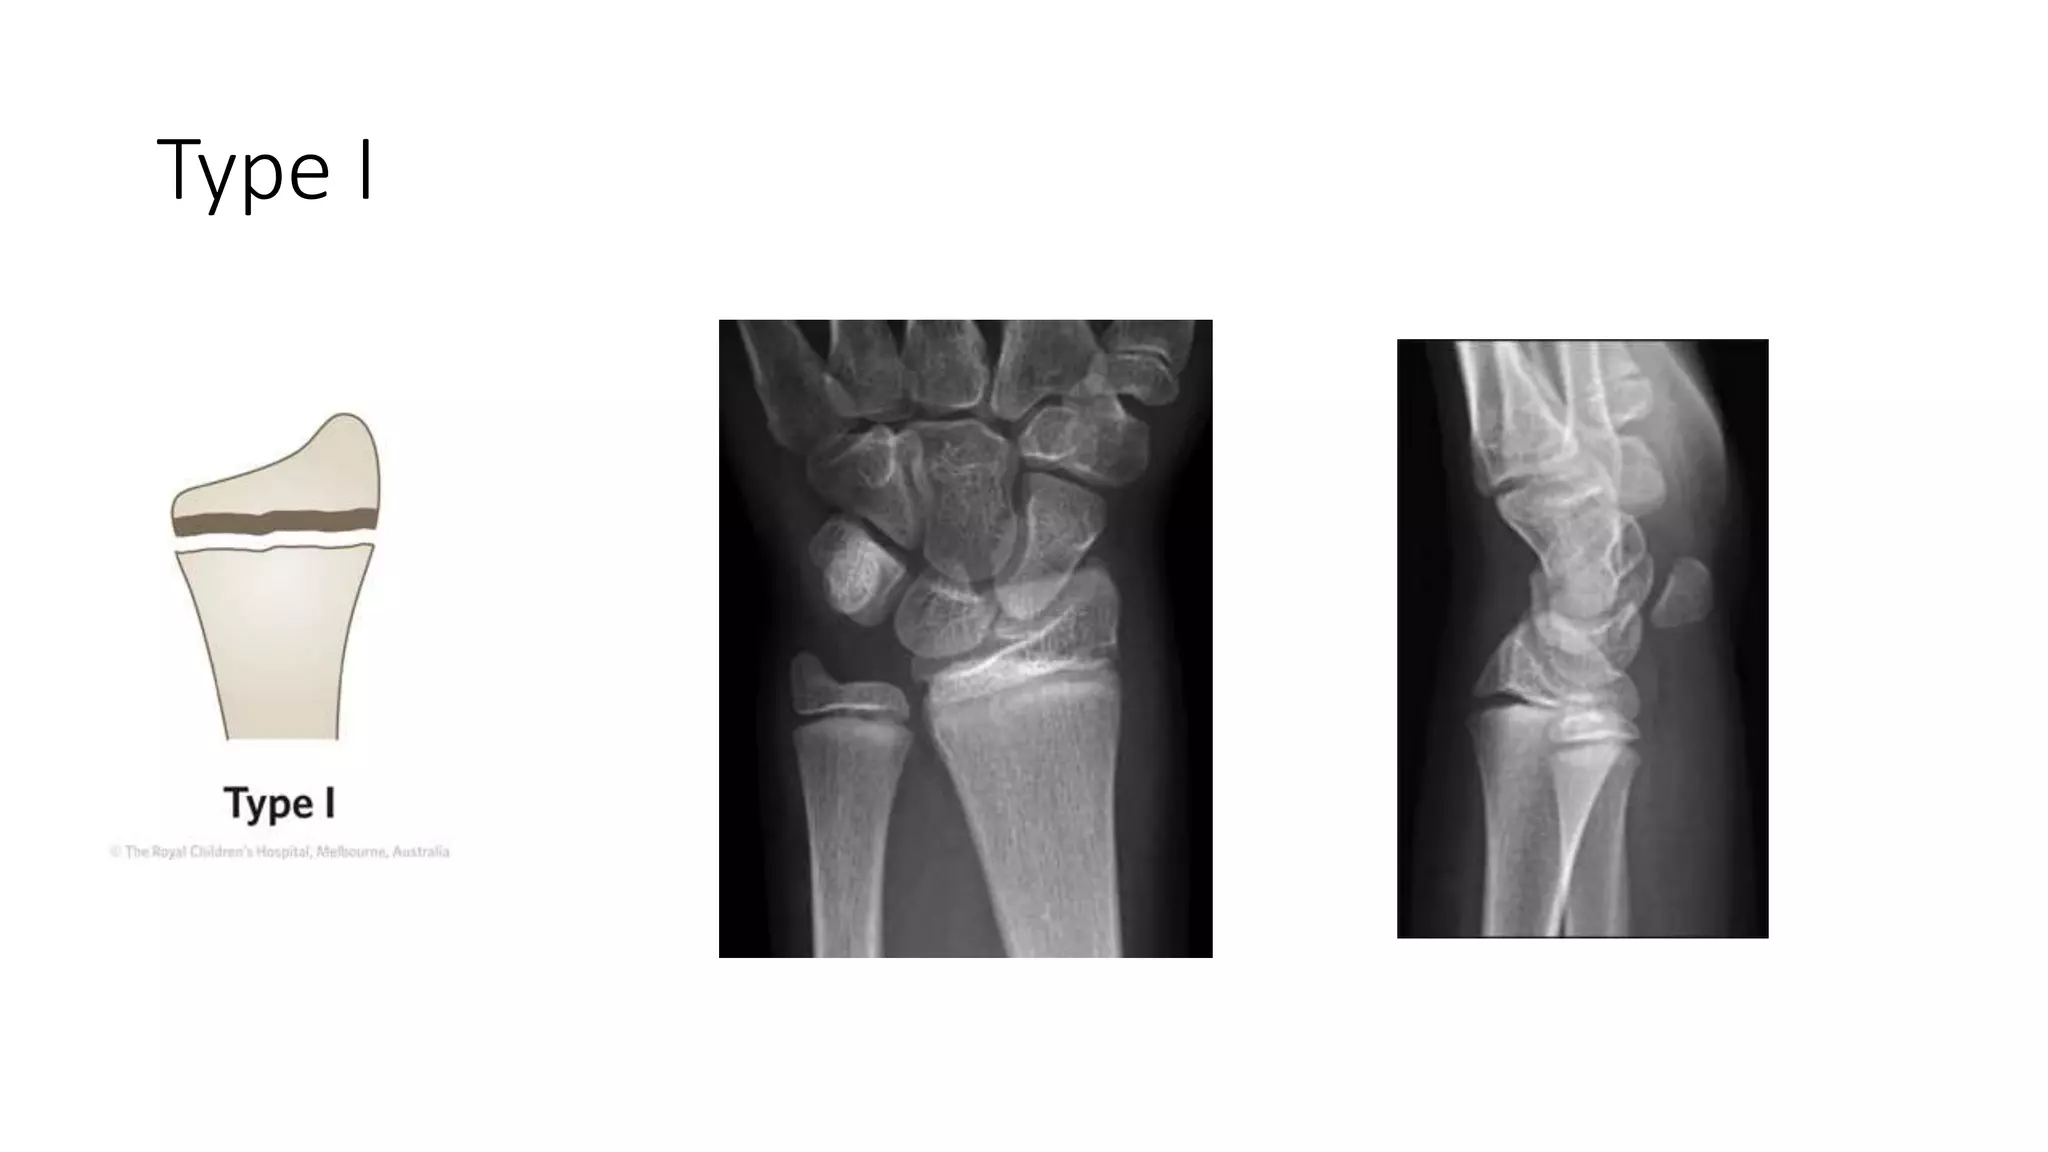

Fractures of the distal radial physis and barton's fracture | PPTX

Fractures of the distal radial physis and barton's fracture | PPT